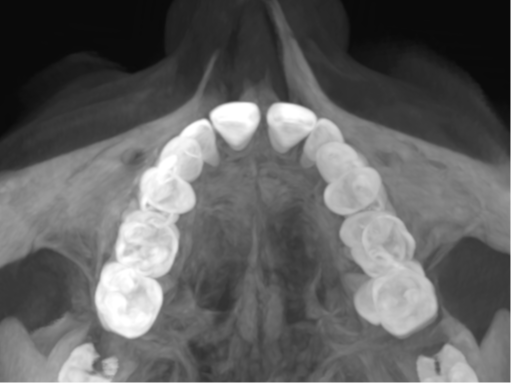

Indications for expansion with braces, RDP or aligners.

Expansion patterns with aligners in Children: case reports

Biomechanics of Dental expansion with aligners: everything you need to know